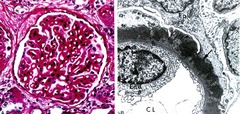

Endodermal Sinus (Yolk Sac) Tumor

Front

Malignant GERM CELL (most common in KIDS) tumor from YOLK SAC *Schiller-Duval bodies (glomerular-like) Tumor markers: AFP